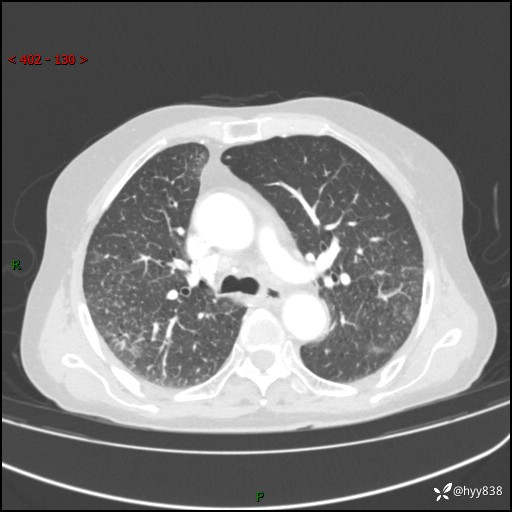

胸部CT增强(外院平扫)